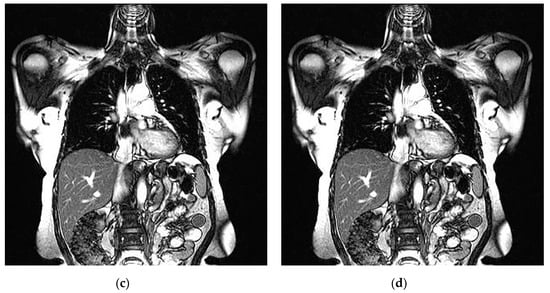

An example of 3D tomographic images “wmri”, “Trufi_COR” and “Body_1.0” DWT with wavelet is shown in Figure 5, Figure 6 and Figure 7 respectively. Frames in Figure 6 and Figure 7 are selected to illustrate the error effect on the image processing result. Figures show a gradual improvement in the quality of processing with an increase the bit-width : in Figure 5b, Figure 6b and Figure 7b visible distortion (Figure 5b is darkened in places, and Figure 6b and Figure 7b are lighted); in Figure 5c, Figure 6c and Figure 7c processed images are indistinguishable by eye from the original images; in Figure 5d, Figure 6d and Figure 7d processed images are identical to the corresponding originals. Experimental results are of higher quality compared with the calculation results. The values dB and at and respectively (Figure 5) obtained after 8-bit image “wmri” DWT with wavelet exceed the corresponding calculated values dB and at and respectively (Table 1). The values dB and at and respectively (Figure 6) obtained after 12-bit image “Trufi_COR” DWT with wavelet exceed the corresponding calculated values dB, dB at and respectively (Table 2). Similarly, for “Body_1.0”.

Example of 3D tomographic 12-bit image “Trufi_COR” (15-th frame) DWT by wavelet: (a) original image; processed image: (b) , dB; (c) , dB and (d) , .

Figure 7.

Example of 3D tomographic 16-bit image “Body_1.0” (1-st frame) DWT by wavelet: (a) original image; processed image: (b) , dB; (c) , dB and (d) , .

The darkening and lighting in Figure 5, Figure 6 and Figure 7 were due to the low accuracy of wavelet filters coefficients quantization used for image processing. The excessive character of quantization error led to an increase in the voxels brightness values of the processed images. Figure 6b and Figure 7b turned out to be lighted since 12- and 16-bit images had a brightness margin, which is shown by the histograms in Figure 4b,c. However, the range of brightness values of the 8-bit image was fully utilized (Figure 4a) and the quantization error led to the computational range overflow. The voxels brightness values that exceeded the range went to zero as a result of this.